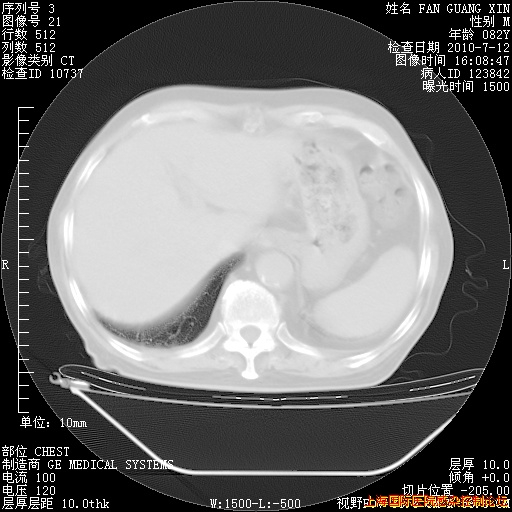

补发6月12日肺部CT肺窗

6月12日肺窗